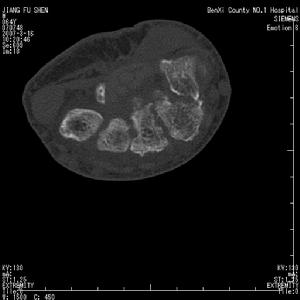

腕關節結核X線表現滑膜型早期可見腕骨小梁模糊,皮質密度變淡,輪廓不完整。晚期由於骨皮質消失及皮質下侵蝕,腕骨可變小。骨型病灶首先開始於橈骨遠端,其次為腕骨(如舟骨、大多角骨、頭狀骨及三角骨),很少繼發於尺骨。病灶常為多發,呈類圓形或不規則形骨缺損,很少有死骨。晚期關節間隙均變窄,病變嚴重者可侵及第2、3掌骨基底部,甚至可達骨幹,可伴有輕度骨質增。生及骨膜反應。病骨往往呈膨脹改變。腕骨結核常合併腱鞘結核,有時可見斑點狀鈣化。兒童的腕關節結核,患側化骨核出現較早。

腕關節結核--CT腕月、舟骨缺血性壞死骨密度增高,有時可見囊變,或呈不規則碎裂。腕關節一般無狹窄,亦無骨破壞。